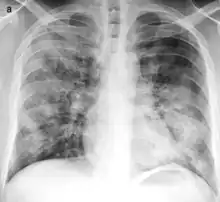

X-ray of bronchopneumonia: multifocal lung consolidation bilaterally.[3]